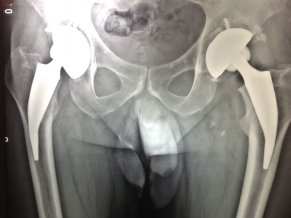

Medicos Argentinos presentan una revolucionaria técnica para tratar la artrosis de cadera

El Dr. Alejandro Druetto, especialista en cirugía de cadera y rodilla, viajó a Dubai para presentar un innovador y efectivo procedimiento para quienes padecen esa dolencia. “Somos el único grupo médico de Argentina...